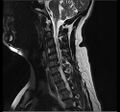

- التصوير بالرنين المغناطيسي هي الدراسة المعيارية الذهبية لتأكيد الاشتباه في انزلاق غضروفي. مع دقة تشخيصية تبلغ 97%، فهي الدراسة الأكثر حساسية لتصور الانزلاق الغضروفي بسبب قدرتها الكبيرة على تصور الأنسجة الرخوة. كما يتمتع التصوير بالرنين المغناطيسي بموثوقية أعلى بين المراقبين مقارنة بوسائل التصوير الأخرى. ويشير إلى انزلاق غضروفي عندما يظهر إشارة متزايدة مرجحة بـ T2 عند المنطقة الخلفية التي تغطي 10% من القرص. وقد أظهرت أمراض الانزلاق الغضروفي ارتباطًا بتغيرات النوع 1 من مقياس موديك. عند تقييم اعتلالات الجذور العصبية القطنية بعد الجراحة، فإن التوصية هي إجراء التصوير بالرنين المغناطيسي مع التباين ما لم يكن هناك موانع أخرى. يعد التصوير بالرنين المغناطيسي أكثر فعالية من التصوير المقطعي المحوسب في التمييز بين الأسباب الالتهابية أو الخبيثة للانزلاق الغضروفي. يُشار إليه في وقت مبكر نسبيًا في مسار التقييم (<8 أسابيع) عندما يظهر المريض مؤشرات نسبية مثل الألم الشديد والعجز الحركي العصبي ومتلازمة ذيل الفرس. التصوير الموتر الانتشاري هو نوع من تسلسل التصوير بالرنين المغناطيسي المستخدم للكشف عن التغيرات الدقيقة في جذر العصب. قد يكون مفيدًا في فهم التغييرات التي تحدث بعد أن يضغط القرص القطني المنفتق على جذر العصب، وقد يساعد في التمييز بين المرضى الذين يحتاجون إلى تدخل جراحي. في المرضى الذين لديهم شكوك عالية في اعتلال الجذور العصبية بسبب الانزلاق الغضروفي القطني، ومع ذلك فإن التصوير بالرنين المغناطيسي غامض أو سلبي، يوصى بدراسات التوصيل العصبي.[44] توفر الصور المرجحة الناتجة عن التصوير بالرنين المغناطيسي (T2) تصور واضح لمادة القرص البارز في القناة الشوكية.

التصوير بالرنين المغناطيسي للانزلاق الغضروفي العنقي بين الفقرتين العنقيتين لخامسة والسادسة.

-

التصوير بالرنين المغناطيسي للانزلاق الغضروفي العنقي بين الفقرتين العنقيتين السادسة والسابعة.